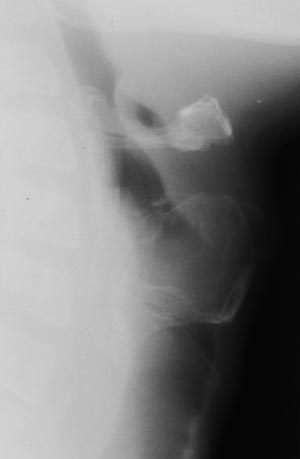

Рис. 2. Томограммы гортани. Посттравнматическая деформация гортани.